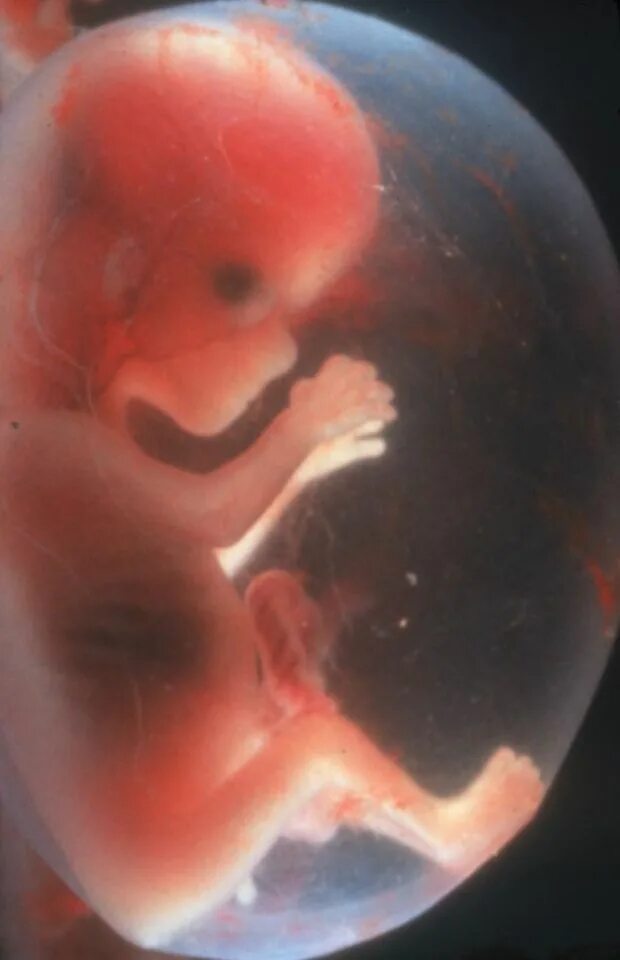

Как выглядит 16 неделя беременности фото